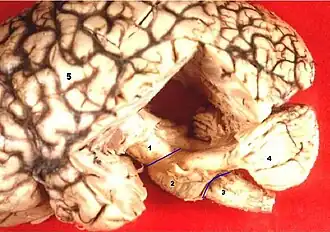

1. śródmózgowie 2. most 3. rdzeń przedłużony 4. móżdżek 5. kresomózgowie

Mózgowie dorosłych osobników utworzone jest z pięciu pęcherzyków mózgowia występujących u embrionu. Są to[2]:

- kresomózgowie (telencephalon)

- międzymózgowie (diencephalon)

- śródmózgowie (mesencephalon)

- tyłomózgowie lub móżdżek (metencephalon lub cerebellum)

- rdzeniomózgowie (rdzeń przedłużony) (myelencephalon lub medulla oblongata)